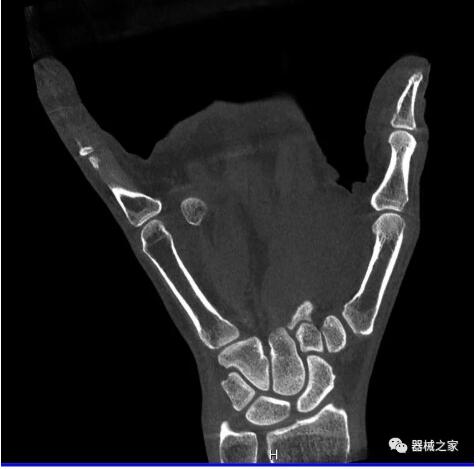

另外一款被稱為世界上最小的CT,它的重量僅300磅,不僅能夠掃查足部,還可以檢查膝蓋和上肢等。

與上面介紹的CT一樣,它同樣具有輻射低、占地空間?。?3*36)的特點,隨開隨用(支持直接接入墻上的插座)。

這款CT使用非常方便,通過上下移動保持與患者的手臂或者雙腿齊平,掃描快速,僅需要30秒左右就可以完成掃查。

以上介紹的CT均來自國外同一家公司,這些CT均配置了可視化軟件,可以進行切片、3D重建以及大型CT附帶的所有典型的操作功能。

以下是這些“特立獨行”的CT所拍出來的圖像: